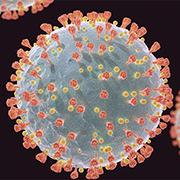

For more than a decade, scientists using the Advanced Photon Source—a U.S. Department of Energy Office of Science user facility at DOE’s Argonne National Laboratory—have been making pivotal discoveries that are helping in the battle against COVID-19.

A new drug candidate, Paxlovid, which has proven to be effective against the SARS-CoV-2 virus, and a superionic ice that is neither liquid nor solid, both based on research at the Advanced Photon Source, are featured in the November 15, 2021 issue of the U. S. Department of Energy “Communique” e-newsletter.

Scientists at Pfizer created Paxlovid, a new drug candidate that proved to be effective against the SARS-CoV-2 virus, which causes COVID-19, with the help of the U.S. Department of Energy’s (DOE’s) Advanced Photon Source at the DOE’s Argonne National Laboratory.